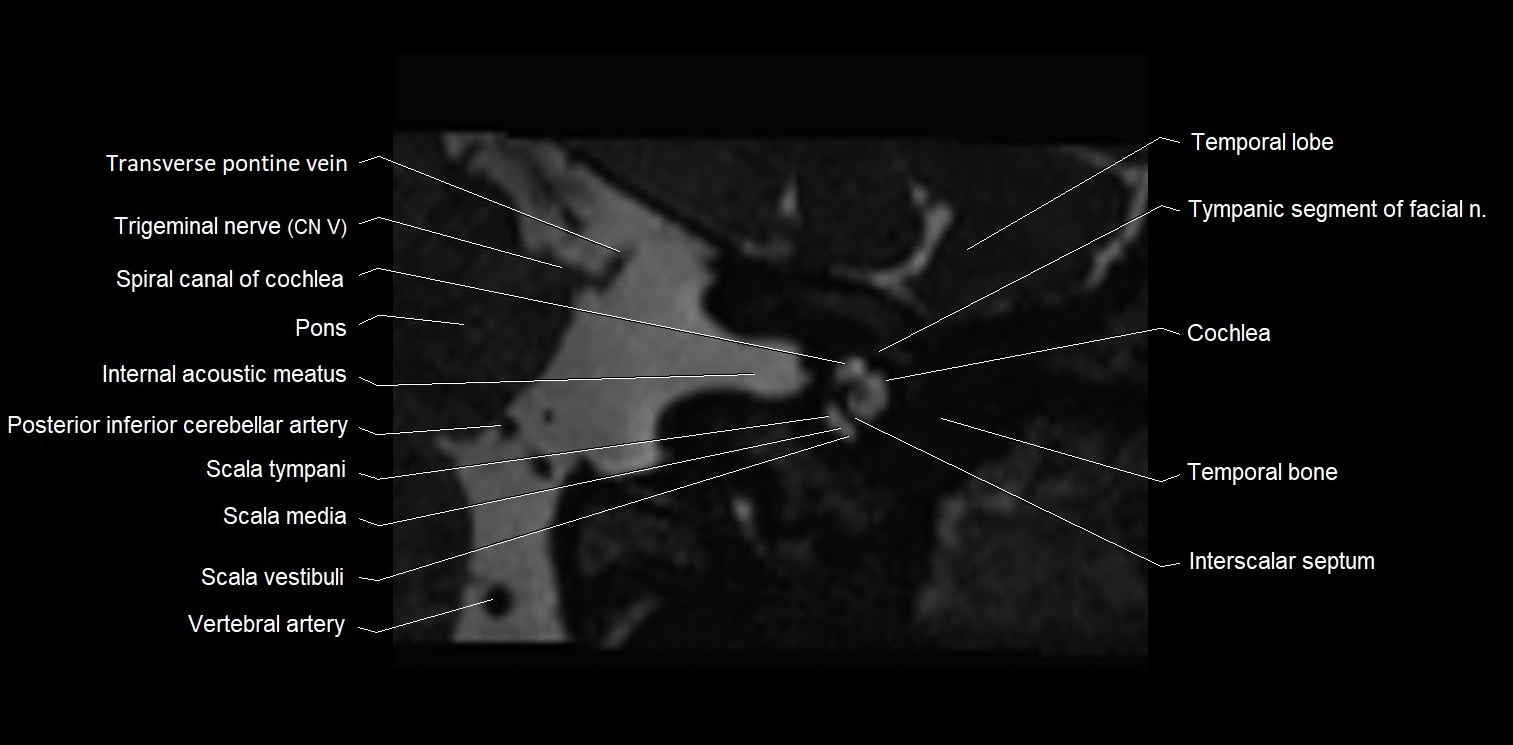

MRI images

image